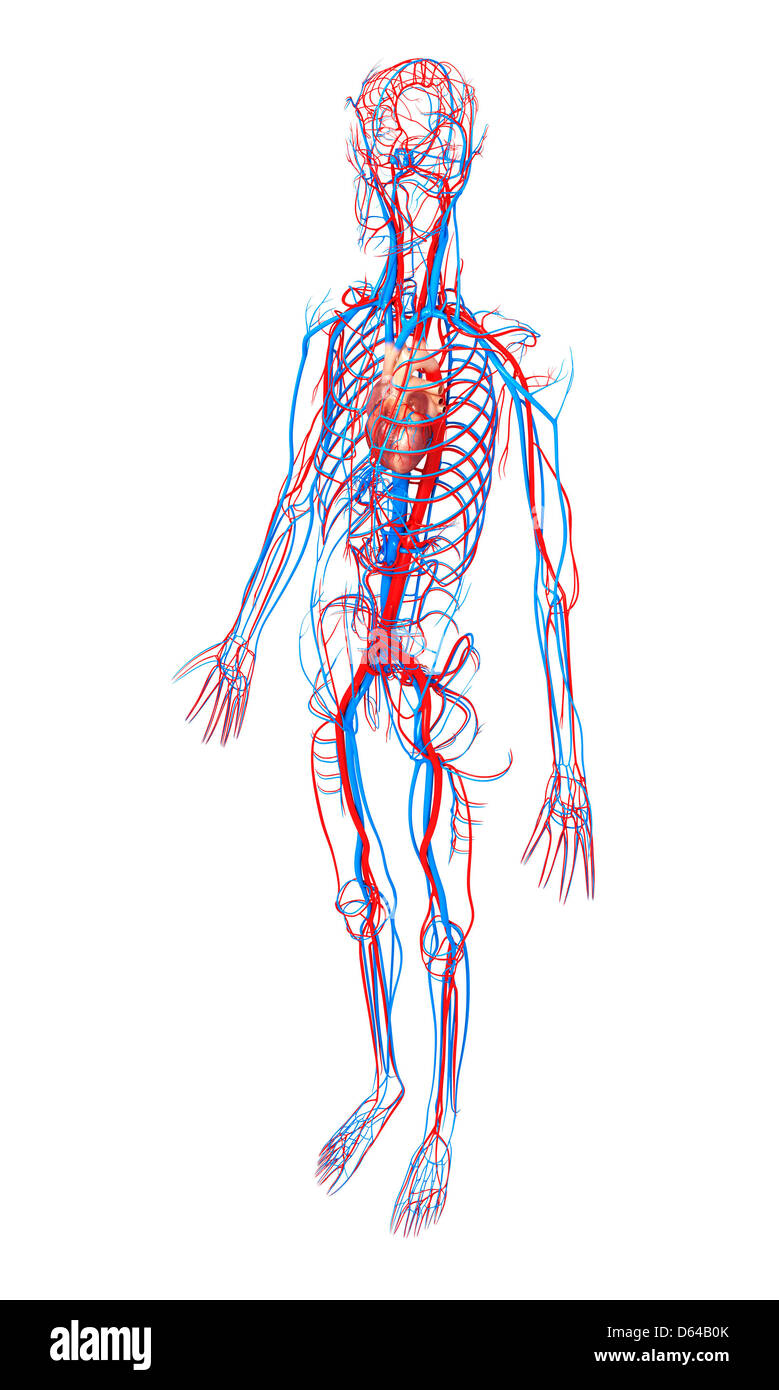

Système cardiovasculaire, artwork Banque D'Imageshttps://www.alamyimages.fr/image-license-details/?v=1https://www.alamyimages.fr/photo-image-systeme-cardiovasculaire-artwork-55415491.html

Système cardiovasculaire, artwork Banque D'Imageshttps://www.alamyimages.fr/image-license-details/?v=1https://www.alamyimages.fr/photo-image-systeme-cardiovasculaire-artwork-55415491.htmlRFD64B0K–Système cardiovasculaire, artwork